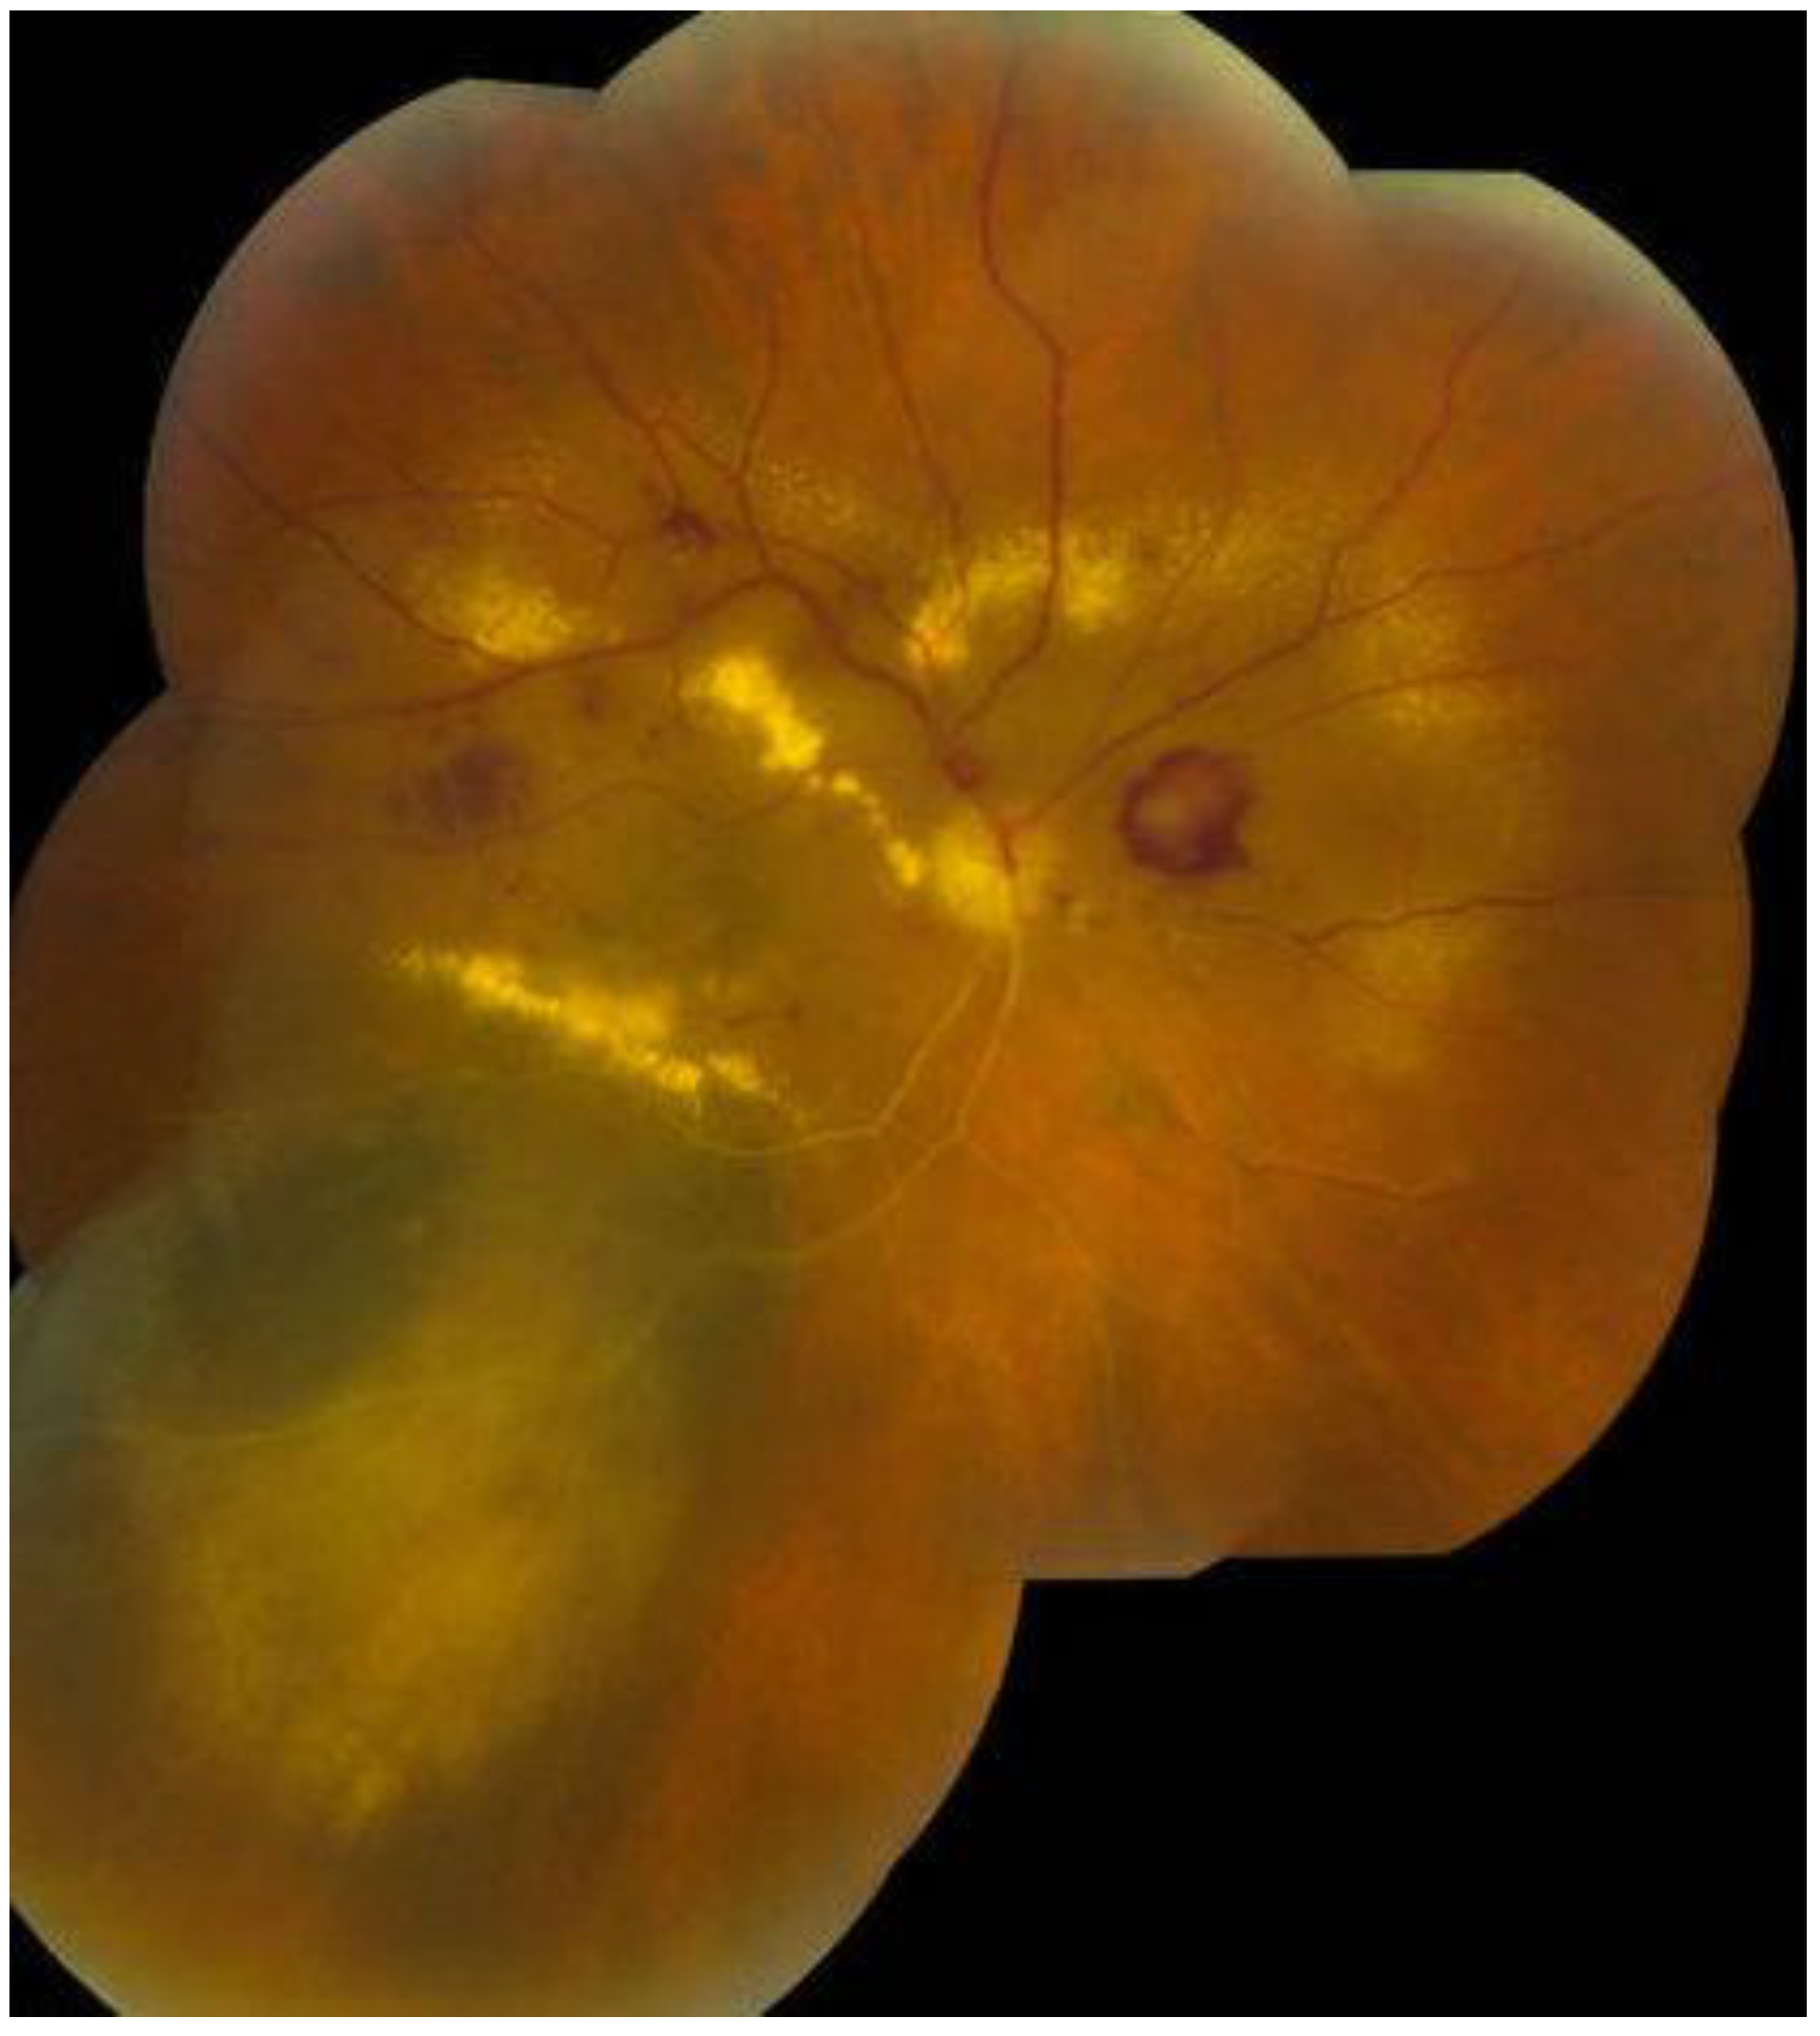

6. History

7. Physical Examination and Evaluation